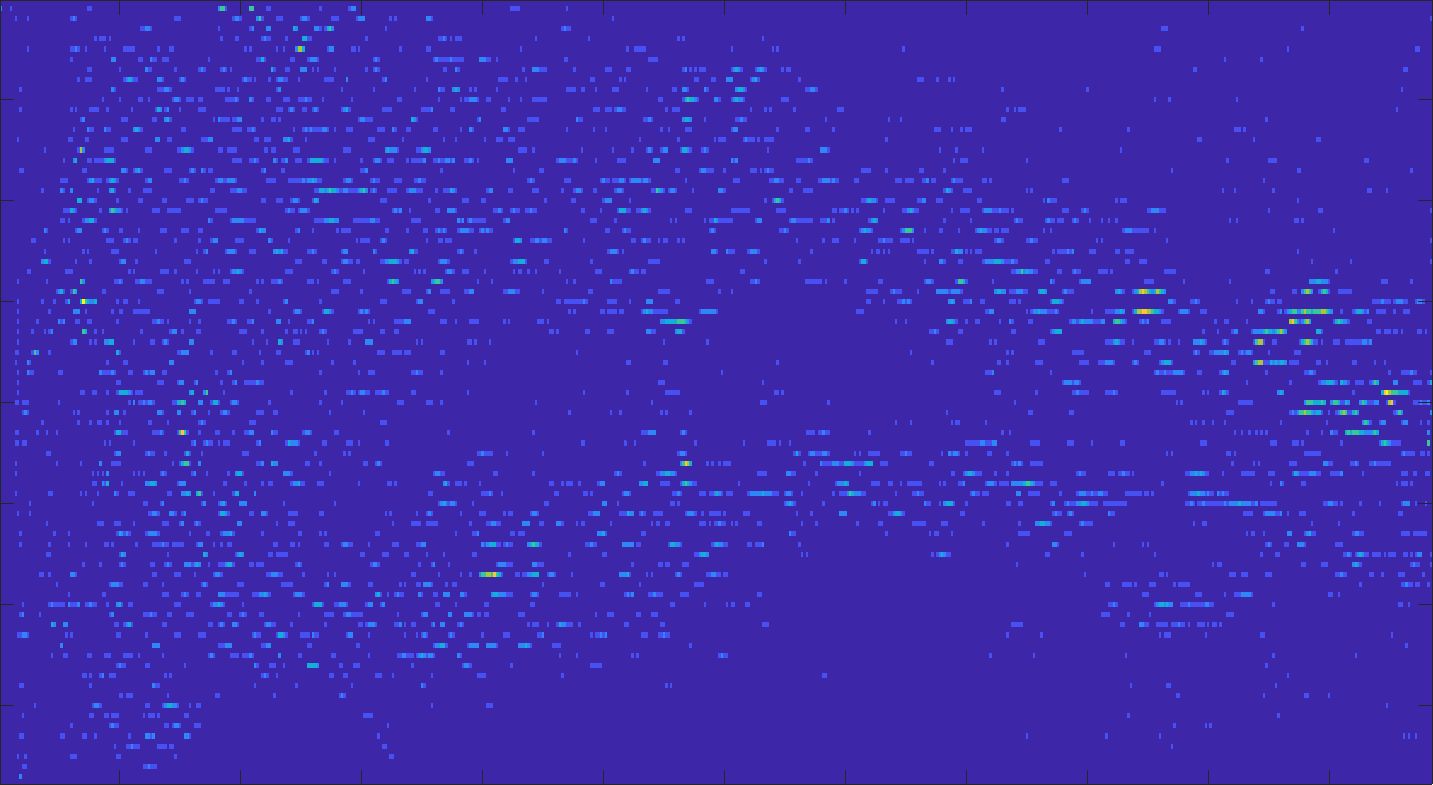

Our framework visually improves the results, in terms of blurring and artefacts. This result is more evident in the magnification of the ear of the foetus (Fig. 3), the mitral valve (Fig. 4), and the mass edges (Fig. 5). Fig. 6 shows the error image of the three anatomical districts with both 2X and 4X up-sampling factors, with the maximum error in the scale . The error is more evident in the contours of the anatomical structures; moreover, the abdominal district shows a smaller error than the cardiac and obstetric ones. We underline that the view for each image is scaled to its maximum, to improve the visualisation of the error.

The analysis of the absolute value of the difference between the input and the prediction of the network (Fig. 9) shows that the alteration of our prediction to the pixel values ranges from 0 to a maximum absolute value of 20, mainly located on the edges of the anatomical structures; furthermore, the black uniform areas are less affected by the prediction. In terms of the distance between the input and the prediction, we do not observe a significant difference among anatomical districts and between 2X and 4X up-sampling.